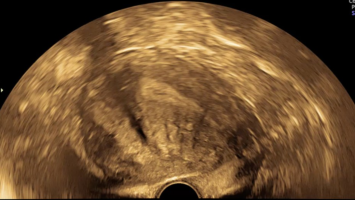

Springer Medizin Podcast - Endometriose/© (M) Willer D. et al. / all rights reserved Springer Medizin Verlag GmbH Logo: Springer Medizin Verlag GmbH, Ärztin misst Blutdruck bei Schwangeren/© Andrey Popov / Stock.adobe.com (Symbolbild mit Fotomodell), Schwangere Frau hält Tablette und Glas Wasser/© NDABCREATIVITY / stock.adobe.com (Symbolbild mit Fotomodell), Justiz/© hawi_101 / Fotolia, CT des Uterus einer 47-Jährigen /© Rizos A et al. | all rights reserved Springer Medizin Verlag GmbH, Gardnerella spp. bedeckte Schlüsselzellen/© Swidsinski A et al. / all rights reserved Springer Medizin Verlag GmbH, Impfung/© Remains / Getty Images / iStock (Symbolbild mit Fotomodellen), Junge Frau sitzt auf Toilette/© Dragana Gordic / stock.adobe.com (Symbolbild mit Fotomodell), Spritze wird aufgezogen/© scyther5 / Getty Images / iStock, Ultraschall der "kissing ovaries" bei Endometriose/© Willer D. et al. / all rights reserved Springer Medizin Verlag GmbH, Ärztin führt Ultraschall bei einer Frau durch/© satyrenko / stock.adobe.com (Symbolbild mit Fotomodellen), Doxy-PEP/© Tobias Arhelger / stock.adobe.com, Junge Frau zur Beratung bei Ärztin/© demaerre / Getty Images / iStock (Symbolbild mit Fotomodellen), Schwangere macht Gymnastik/© fotostorm / Getty Images / iStock (Symbolbild mit Fotomodell), Junge Patientin im Gespräch mit einer Ärztin/© FatCamera / Getty Images / iStock (Symbolbild mit Fotomodellen), Urogenitale Fistel bei einer 36-jährigen Patientin/© Lautenschlager S et al. / exklusiv lizenziert an Springer-Verlag GmbH Austria, ein Teil von Springer Nature 2024, CT bei endometrioidem Karzinom/© Kuzinska MZ et al. / all rights reserved Springer Medizin Verlag GmbH, Frau nimmt Diaphragma in der Hand/© AndreyPopov / Getty Images / iStock (Symbolbild mit Fotomodellen), Ein Abstrich vom Gebärmutterhals wird auf ein Objektivträger geschmiert/© Tatiana Buzmakova / Getty Images / iStock (Symbolbild mit Fotomodellen), Frau nutzt Pen am Bauch/© bung / Stock.adobe.com (Symbolbild mit Fotomodell), Reife Eizelle im Mikroskop/© S. Al-Hasani, Podcast mit Partnern - Roche STI/© (M) Aleksej / stock.adobe.com; Logo: Springer Medizin GmbH, Titelbild Kongress Kompakt EADV 2024/© Hintergrundbild: gnoparus / stock.adobe.com, Search Icon, Paar schaut glücklich auf Schwangerschaftstest/© Andrii Zastrozhnov / Stock.adobe.com (Symbolbild mit Fotomodellen), ZFA TALKS - Depression/© (M) seb_ra / Getty Images / iStock (Symbolbild mit Fotomodell) Logo: Springer Medizin Verlag GmbH, Ältere Frau fasst sich an die Brust/© Jelena Stanojkovic / Stock.adobe.com (Symbolbild mit Fotomodell), Person setzt DNS-Probe in Maschine ein/© Vit Kovalcik / stock.adobe.com